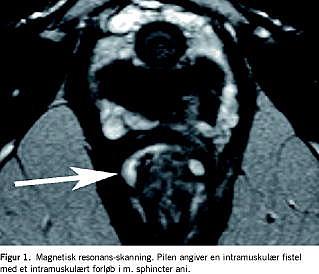

III. En 36-årige kvinde havde haft kendt stenoserende og fistulerende tyndtarms-morbus Crohn siden 1993. Patienten havde fået foretaget resektion af colon ascendens, caecum og i alt 40 cm af ileum og var i profylaktisk behandling med 50 mg azathioprin dagligt. Hun havde tidligere fået behandling med infliximab i 2001, men hun fik under den anden infusion anafylaksilignende reaktion med åndenød. I 2004 fik hun igen mavesmerter, 10-15 vandtynde afføringer i døgnet med pus og slim samt intermitterende subiliusgener. En røntgenundersøgelse af tyndtarmen viste recidiv i den neoterminale ileum. Derudover havde hun afgang af flatus og fæces ad vagina, og en magnetisk resonans (MR)-skanning viste forgrenet fistelgangssytem i analkanalens væg med udløbere til vagina og rectum.